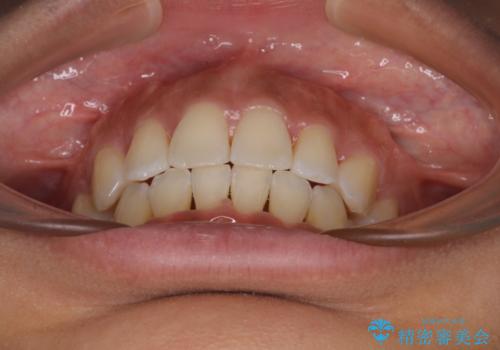

- 下唇が突き出るような口元の突出感が気になるとのことで来院された患者様です。

上下顎ともに前突した歯列であったので、上下ともに左右の第1小臼歯4本を抜歯し、ワイヤー装置にて矯正治療を行うこととしました。

抜歯スペースに前歯を移動させることで歯の突出感が改善され、非常に唇が閉じやすい仕上がりとなりました。